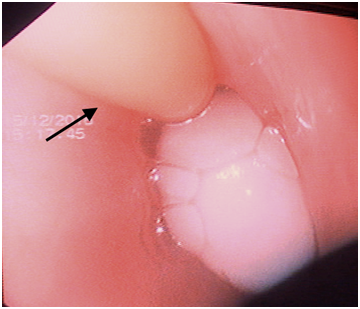

Figure 2 Endoscopic picture of Foley catheter (arrow) retrieving the foreign body.

An esophagoscopy done under general anaesthesia revealed a white, round marble stone impacted at the mid-oesophagus. Forceps/snare removal was not successful because of the round shape and smooth surface of the stone. A 14 Fr Foley catheter was guided post foreign body and balloon was inflated with 5 ml saline. The Foley catheter was gradually pulled out along with the stone under endoscopic vision. The intermittent suction applied endoscopically also helped dislodgement and proximal movement of the stone. The stone was then brought to the oral cavity from where it was finally removed. Check endoscopy showed intact esophageal mucosa. The patient was given oral diet after recovering from anaesthesia, which she tolerated well. She was discharged from the hospital next day.

Despite having several advantages, non-endoscopic techniques are not widely accepted in the western practice as they do not allow direct visualization the esophagus and there is theoretical risk of severe complications such as broncho-aspiration, esophageal perforation, and acute airway obstruction. For these reasons, it is recommended that removal of foreign bodies should be carried out under direct vision with airway protection, especially in the paediatric age group.1 In our case, we used a 14 Fr Foley catheter and stone was retrieved under direct vision of a flexible endoscope while protecting the airway, therefore completely eliminating the blind nature of fluoroscopic Foley catheter technique. Also, since Foley catheter was used in place of an expensive endoscopic esophageal balloon, the cost of the procedure was significantly decreased.